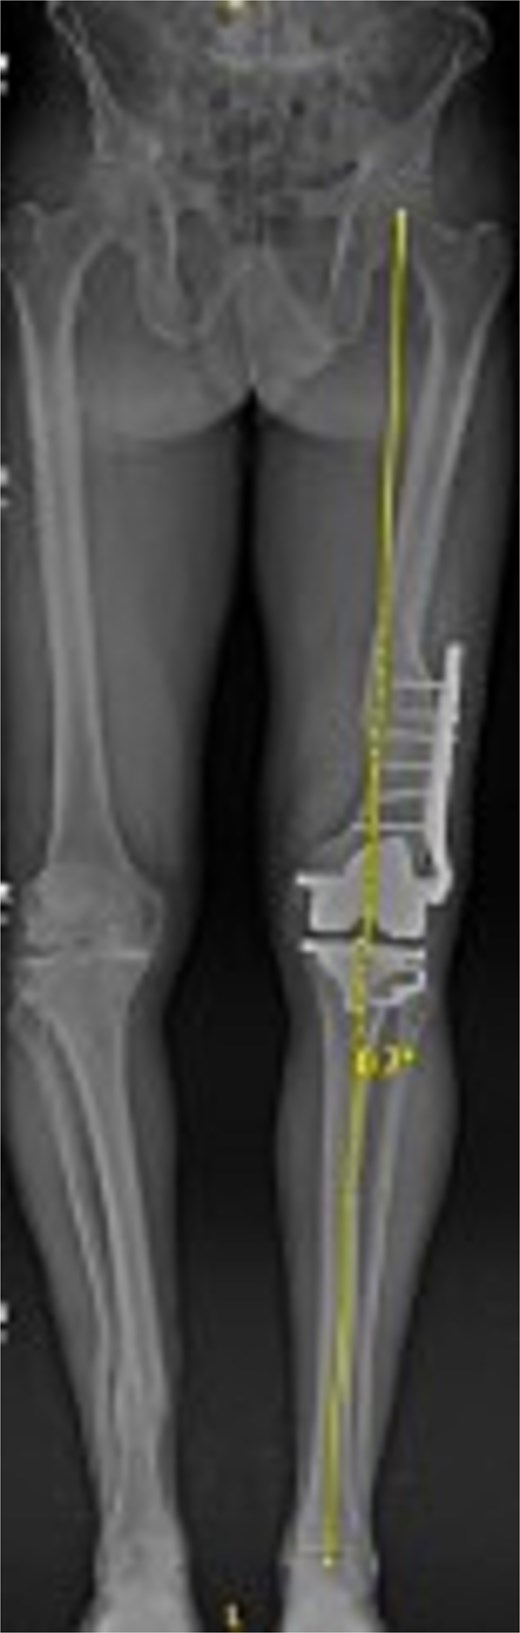

Figures 3 and 4 show a postoperative lateral and AP radiograph of the left knee. The patient was able to fully extend his knee after surgery and instructed to weight bear as tolerated until his two-week follow-up. Patient-reported outcome measures were completed at 2 year follow up (Table 1) with no reported complaints or issues at that time.

Postoperative AP bone length films 1 year after robotic-assisted TKA with hardware retention. The new femoral and tibial components are in place. The retained femoral plate is visible along the lateral cortex of the femur. Postoperative mechanical alignment of the left leg is 0.7°.